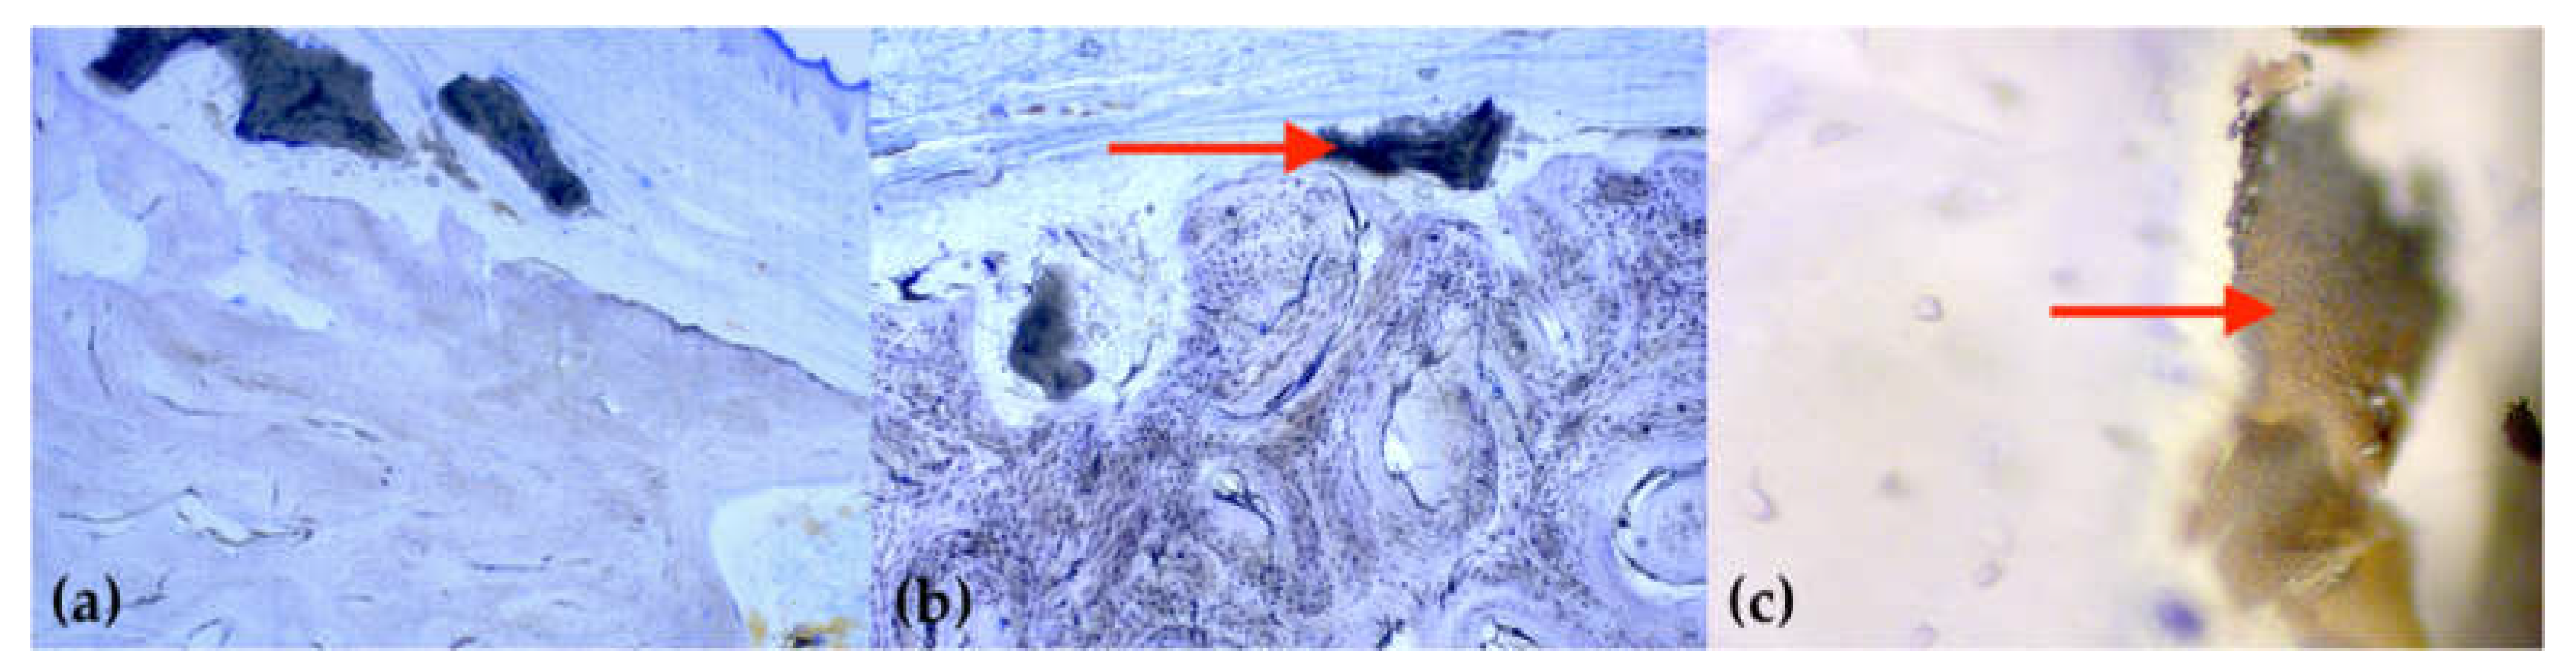

2.3. Histology

- Fischer, K.R.; Stavropoulos, A.; Calvo-Guirado, J.L.; Schneider, D.; Fickl, S. Influence of local administration of pamidronate on extraction socket healing—A histomorphometric proof-of-principle pre-clinical In Vivo evaluation. Clin. Oral Implant. Res. 2015, 26, 1135–1142. [Google Scholar] [CrossRef]

- Lozano-Carrascal, N.; Delgado-Ruiz, R.A.; Gargallo-Albiol, J.; Maté-Sánchez, J.E.; Hernandez Alfaro, F.; Calvo-Guirado, J.L. Xenografts supplemented with Pamindronate placed in postextraction sockets to avoid crestal bone resorption. Experimental study in Fox hound dogs. Clin. Oral Implant. Res. 2016, 27, 149–155. [Google Scholar] [CrossRef]

- Cha, J.K.; Sun, Y.K.; Kim, M.J.; Sanz, M.; Jung, U.W. Anti-Resorptive effect of pamidronate on extraction socket wall in dogs. Clin. Oral Implant. Res. 2018, 29, 688–696. [Google Scholar] [CrossRef] [PubMed]